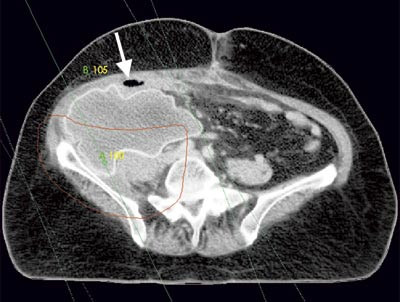

Pasienten. En tidligere frisk kvinne ble som 68-åring operert for cancer coeci med perforasjon. Det forelå en perikolisk abscess, og det ble gjort høyresidig hemikolektomi med reseksjon av fremre bukvegg. Inngrepet ble ansett som radikalt. I operasjonspreparatet fant man spredning til regionale lymfeknuter (Dukes C), og hun fikk derfor adjuvant kjemoterapi med 5-fluorouracil/leukovorin i seks måneder. Ett år senere utviklet hun sterke smerter i høyre flanke med utstråling til høyre lår, og ved CT ble det påvist en 12 cm stor tumor som infiltrerte m. iliopsoas dexter, oppfattet som et lokoregionalt residiv (fig 1). Det var ingen fjernmetastaser. Residivet ble resecert i muskulatur ved laparotomi, men tumorvev måtte etterlates omkring iliacakarene. Svulsten omsluttet n. femoralis, som måtte deles. Tumorsengen ble markert med metallklyper, og en brystprotese i silikon ble lagt på reseksjonsflaten for å skyve tynntarmen vekk fra det påtenkte strålefeltet (fig 2). Postoperativ CT viste likevel en interponert tarmslynge mellom protesen og fremre bukvegg (fig 3). Seks uker etter inngrepet ble det påbegynt radiokjemoterapi med 2 Gy x 25 som to motgående skråfelt og strålesensibiliserende 5-fluorouracil/leukovorin (fig 3). Under bestrålingen utviklet kvinnen høyresidig bekkenvenetrombose, og hun fikk antikoagulasjonsbehandling. Radioterapien var ledsaget av periodevise buksmerter, men uten diaré eller andre tegn til akutt stråleenteritt. Åtte uker etter endt bestråling ble hun igjen laparotomert. Den nevnte tarmslyngen frembød da ganske uttalte stråleskader. Protesen lot seg fjerne, i hovedsak ved stump disseksjon (fig 4). Pasienten ble likevel påført en ureterskade, som kunne repareres umiddelbart. Det var ingen gjenværende tumor, verken makro- eller mikroskopisk.

Implantasjon av brystproteser for å deplassere tynntarm har tidligere vært anvendt før bekkenbestråling (13, 14); ved abdominal bestråling er det kun rapportert brukt enkelte ganger (15). Mens migrasjon av protesen ikke utgjør noen stor risiko i bekkenet, er faren for dette større i abdomen. Av frykt for silikonlekkasje unnlot vi å fiksere protesen med suturer, og det viste seg at postoperative adheranser stabiliserte den uten forlenget sengeleie. En sikrere løsning kan være å pakke protesen inn i et resorberbart nett, som så sutureres til nabostrukturer (14). Det anbefales postoperativ kontrastundersøkelse for å kontrollere at tarm ikke interponeres i strålefeltet mellom protesen og tumorsengen eller i strålefeltet mellom protesen og bekken- eller bukveggen (13) – (15). Dette skjedde hos vår pasient, og, som vi kunne konstatere ved relaparotomien, var et tarmsegment blitt stråleskadet. Det er beskrevet flere teknikker for å forhindre dette, både transposisjon av omentum majus og innsying av resorberbare nett (13) – (15). Enkelte forfattere anbefaler saltvannsproteser i stedet for silikonproteser (14, 15). Fra et strålefysisk synspunkt er saltvannsproteser kanskje bedre egnet (16). Viktigere er det nok at en slik protese kan fylles i varierende grad slik at størrelsen kan tilpasses, og sist, men ikke minst, at en saltvannsprotese ikke nødvendigvis må fjernes – den kan aspireres perkutant etter endt strålebehandling slik at relaparotomi unngås (14). Fra mammakirurgien er det kjent at implanterte proteser kan være vanskelige å ekstirpere, og selv om implantatet i vårt tilfelle i hovedsak lot seg dissekere ut stumpt, ble pasienten påført en ureterskade under uthentingen. Under strålebehandlingen fikk hun bekkenvenetrombose, sannsynligvis betinget i en kombinasjonen av mekanisk kompresjon fra protesen og bestråling. Dette kunne vært forutsett, og pasienten burde fått tromboseprofylakse.